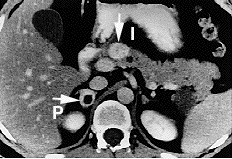

![]() КТ знімок: в голівці підшлункової залози визначається новоутворення - ПанНЕП (стрілка вгорі). Також визначається новоутворення правого наднирника - феохромоцитома. КТ знімок: в голівці підшлункової залози визначається новоутворення - ПанНЕП (стрілка вгорі). Також визначається новоутворення правого наднирника - феохромоцитома. | |